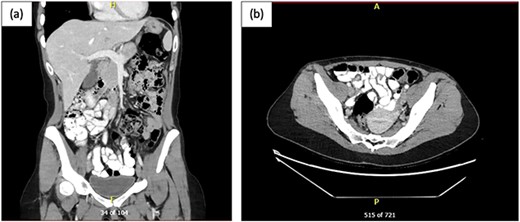

Given the acuity of patient’s severe abdominal pain and generalized tenderness on examination, a computed tomography of the abdomen and pelvis (CT AP) was performed to assess for an acute surgical cause as shown in Fig. 1.

CT AP post oral and intravenous contrast; (a) coronal view and (b) axial view showing multiple mildly dilated small bowel loops, suspicious for developing SBO, with transition point in the right lower pelvis, where there is possible focal mural thickening, and no perforation; the appendix appeared normal.

The CT AP demonstrated an evolving SBO which is consistent with patient’s clinical symptoms and presentation; however, the small bowel showed a maximal diameter of only 2.4 cm. General Surgery team was consulted promptly and instigated management involving insertion of a nasogastric tube (NGT) that was on free drainage and 4-hourly manual aspirations, bowel rest, indwelling catheter insertion for strict fluid balance, intravenous fluid resuscitation, and electrolyte optimization. In view of the patient’s pain and generalized tenderness on examination, an evolving SBO on CT AP in a patient with no previous abdominal surgery, a decision was made for urgent diagnostic laparoscopy.